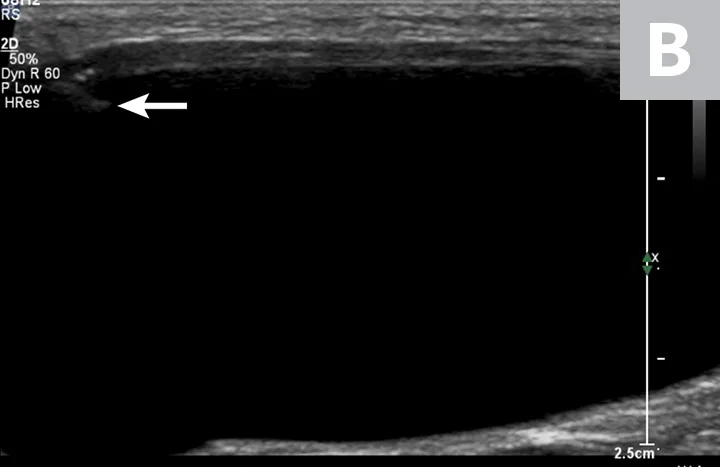

FIGURE 1

Ultrasonographic image showing the cranial aspect of the urinary bladder (A), identified just before ultrasound-guided cystocentesis. It is important to adjust the depth of the image so that the urinary bladder is focused and to consider the depth of the urinary bladder using a machine scale that should be present on the ultrasound screen; in smaller patients the needle may only be partially inserted and not reach the hub (B; arrow).